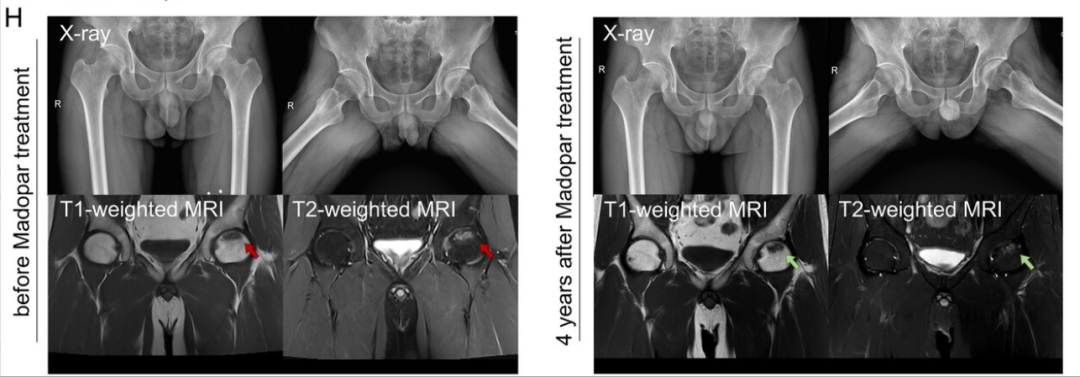

4年临床随访:87%患者股骨头塌陷停滞(对照组仅43%)